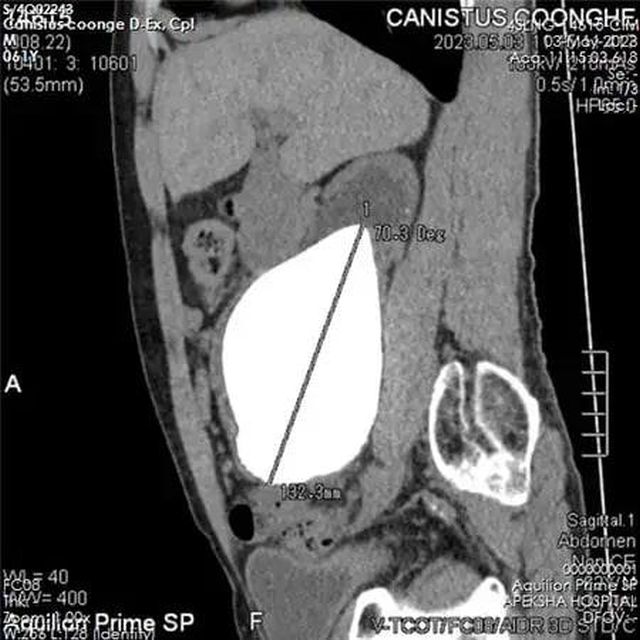

Вес камня составил 801 грамм, а его длина — 13.37 сантиметра! Таким образом, вес этой каменюки в 5 раз превысил вес среднестатистической мужской почки.